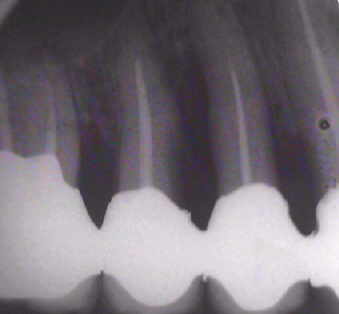

Auffällig ist, dass sich der Erfolg der Maßnahme trotz der ausgesprochen ungünstigen Voraussetzungen eher in Zentimetern als in Millimetern messen lässt, wobei die Sondierungstiefen dem Röntgenbefund entsprechen. Dies, obwohl es sich eher um eine Verzweiflungstat unsererseits gehandelt hat, keine Membran benutzt wurde, lediglich Cerasorb ohne zusätzlichen Eigenknochen eingebracht wurde, es zur zweimaligen Nahtdehiszenz mit anschließender sekundärer Wundheilung kam, man die Caerasorb-Kügelchen längere Zeit klinisch freiliegend beobachten konnte.

Dieser Fall, der eindeutig Lindhes Kriterien entspricht, die zu dieser Meinungsänderung geführt haben, kann jedoch trotz seines ursprünglich sehr dramatischen Verlaufs nach dieser langen Periode des Sistierens jeglicher Parodontitissymptomatik in unseren Augen als ausgeheilt betrachtet werden. Wir sehen eigentlich nicht, warum diese Versorgung nicht zumindest die nächsten 10 Jahre ohne weiteren unphysiologischen Knochenverlust überdauern sollte. Ein anderer Verlauf würde uns aufgrund unserer Erfahrung bei vor langer Zeit sanierten Fällen ausgesprochen überraschen. Dies um so mehr, als das Problem im Bereich 14-15-16 offensichtlich beseitigt ist.